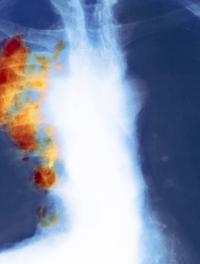

Le cancer bronchique non à petites cellules (CBNPC) est souvent découvert tardivement. A l’heure actuelle, l’indication d’une résection [...]

Le cancer bronchique non à petites cellules (CBNPC) dans sa variété épidermoïde représente 20 à 30 % de tous les cancers bronchiques. [...]

La surveillance scannographique après chirurgie dans le cancer bronchique non à petite cellule repose davantage sur des avis d’experts [...]

L’immunothérapie est indiquée dans les cancers bronchiques non à petites cellules (CNPC) depuis quelques temps maintenant, ce qui permet [...]

Environ un tiers des cancers bronchiques non à petites cellules (CBNPC) sont découverts en stade III, non résécables. Le standard thérapeutique [...]

Parmi les anomalies moléculaires décelables dans les cancers du poumon non à petites cellules (CNPC), le réarrangement du gène ALK [...]

Le cancer pulmonaire de stade III reste de pronostic très sévère. Pour les cancers de stade IIIA/N2, plusieurs schémas thérapeutiques [...]

L’une des caractéristiques du cancer et notamment du cancer bronchique est sa capacité à contourner la réponse immunitaire. PD-1 (programmed [...]

De nombreux patients atteints d’un cancer du poumon sont diagnostiqués à un stade avancé de leur maladie et relèvent d’une chimiothérapie. [...]

Le cancer du poumon à petites cellules (KBP-PC) représente 13 % de l’ensemble des tumeurs malignes pulmonaires. Il est souvent découvert [...]

Le cancer du poumon est une des causes majeures de mortalité spécifique à travers le monde, le plus souvent lors d’un stade tardif [...]

Malgré quelques progrès (assez limités), le pronostic du cancer du poumon non à petites cellules (CPNPC) à un stade avancé (IIIB ou [...]

Le carcinome bronchique est la maladie tumorale la plus fréquente dans le monde. Chez les patients de stade I opérés, la survie est [...]